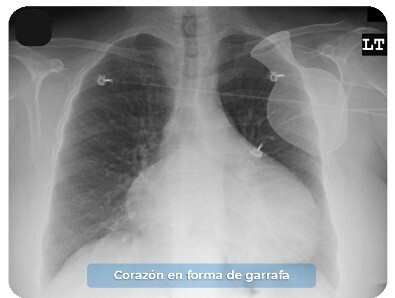

¿ Cual es el hallazgo en la radiografia de tórax caracteristico de la Pericarditis Aguda ?

Corazón con cardiomegalia en forma de garrafa